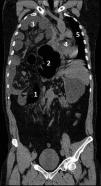

We present the case of a 49-year-old male treated with a hepatectomy due to hydatid cyst 3 years ago. He is admitted to the ER due to short-term intense pain at right renal fossa level; the blood test performed appears normal, and the abdominal ultrasound shows no pathological findings; the abdominal X-ray (Fig. 1) appears normal at the beginning; the medical examination confirms the lack of bowel pattern almost entirely with presence of air bubbles in right hypochondrium and iliac fossa. After being stabilized, the patient is admitted to the hospital floor with signs of nephritic colic. The patient’s clinical status becomes worse after the first 24 h and a TC scan is performed (Fig. 2) that reveals the presence of a large diaphragmatic hernia (1) with perforation and necrosis of large (2) and small intestine (3) accompanied by displacement of all thoracic viscera (4 and 5). Due to the situation of refractory septic shock, 3 surgeries are performed for large intestine resection due to massive ischemia. The patient’s progression is gradually good. He now rests in his home although with signs of short bowel syndrome.